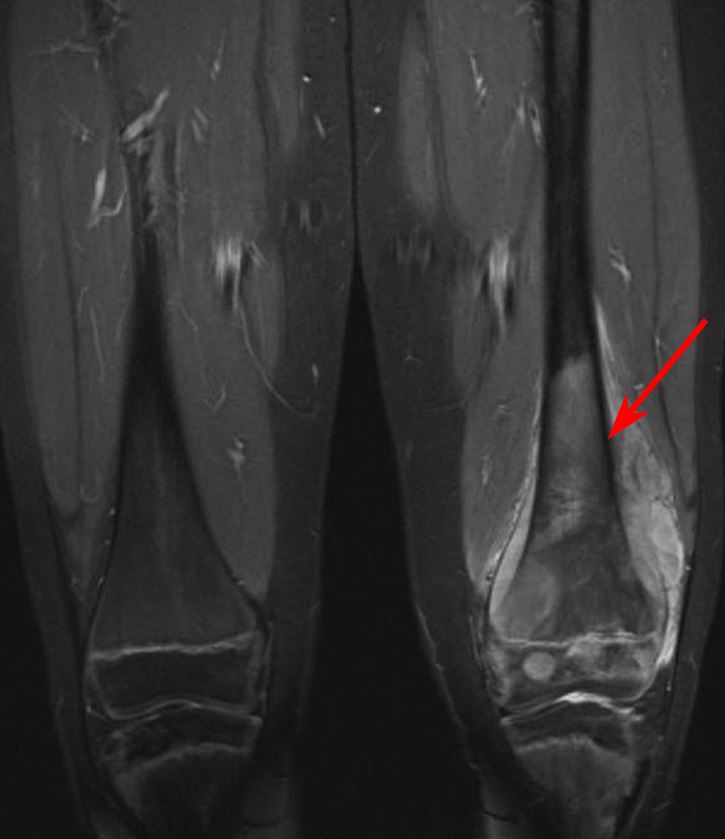

MRI scan of osteosarcoma in thighbone

MRI scan shows an osteosarcoma in the lower left femur (thighbone) of a 10-year-old patient.

Reproduced from Messerschmitt PJ., Garcia RM, Abdul-Karim FW, Greenfield EM, Getty PJ: Osteosarcoma. J Am Acad Orthop Surg 2009; 17:515-527.